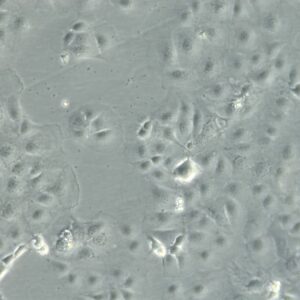

Morphology: Epithelial-like

Growth Properties: Adherent

Description: HuH7 was established in 1982 by Nakabayashi et al. from a 57-year-old Japanese male with well differentiated hepatocellular carcinoma.